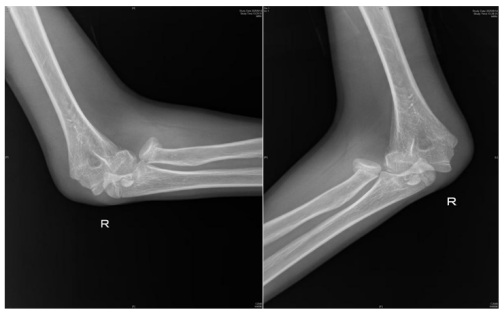

术前检查提示桡骨头骨折,肱骨远端骨折,肘关节脱位

近日,13岁的邓佑(化名)在放学途中,一边看手机一边走路,未留意前方障碍,整个人猛地撞上了护栏,在倒地的瞬间,他用右手撑地,随即感到一阵钻心的剧痛从肘部爆发开来,被紧急送往维多利亚老品牌76696vic(南华大学附属长沙中心医院)手足显微外科就诊。经系统检查,被诊断为:右桡骨头骨折、肱骨内上髁骨折、右肘关节脱位。

“患者入院后,我们紧急行右肘关节脱位复位,肿胀消退后为其设计了尽可能微创的手术方案:右桡骨头骨折闭合复位弹性髓内针内固定+肱骨内上髁骨折切开复位内固定,手术顺利。术后患者恢复良好,即将出院。”据该院手足显微外科主任、副主任医师蒋亮东介绍,医院经常接诊因低头看手机导致意外受伤的患者。其中,桡骨头骨折在青少年人群中尤为常见,它通常是由于在摔倒时手掌撑地,间接暴力传导至肘部而发生的骨折。

人体的肘关节就像一座精密的“协作工厂”,里面住着三位重要“伙伴”—桡骨、尺骨和肱骨。桡骨顶端有一个像“小圆帽”的结构,那就是桡骨头。它相当于肘关节的“旋转轴承”,帮助我们完成转笔、拧瓶盖、拧毛巾等需要前臂旋转的动作。蒋亮东提醒,当我们低头紧盯手机屏幕,不仅注意力高度集中,身体平衡能力也会下降。一旦不慎跌倒,手会本能地支撑地面。此时巨大冲击力会沿手臂向上传导,如同“冲击波”一般直击桡骨头这个“小圆帽”,轻则使其裂缝,重则崩碎成数块。通过X光片,医生可以清晰地看到它的“受伤模样”。